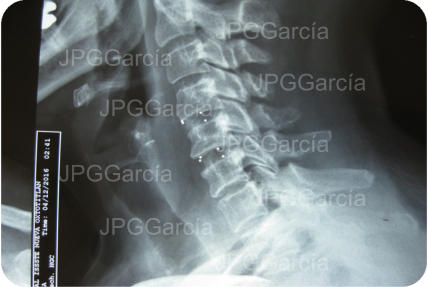

EXTRUSIÓN DE DISCO CERVICAL C4-C5